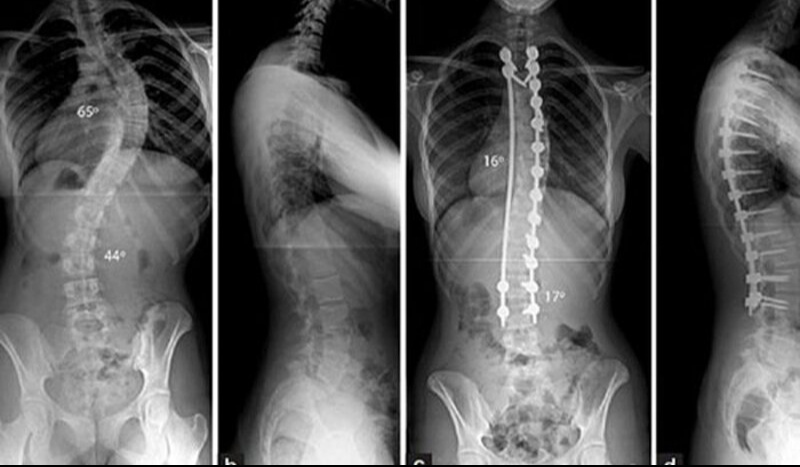

Chụp X quang cột sống là một phương pháp dùng hình ảnh để chẩn đoán rất phổ biến và quan trọng trong y học. Được sử dụng để đánh giá và chẩn đoán các vấn đề liên quan đến cột sống và các cấu trúc xương xung quanh. Phương pháp này cung cấp hình ảnh hai chiều của cột sống, cho phép bác sĩ đánh giá kích thước, hình dạng và vị trí của các đốt sống và mô mềm xung quanh. Chụp X quang cột sống thường được sử dụng để:

Dưới đây là một số bệnh có thể được chẩn đoán thông qua chụp X quang: